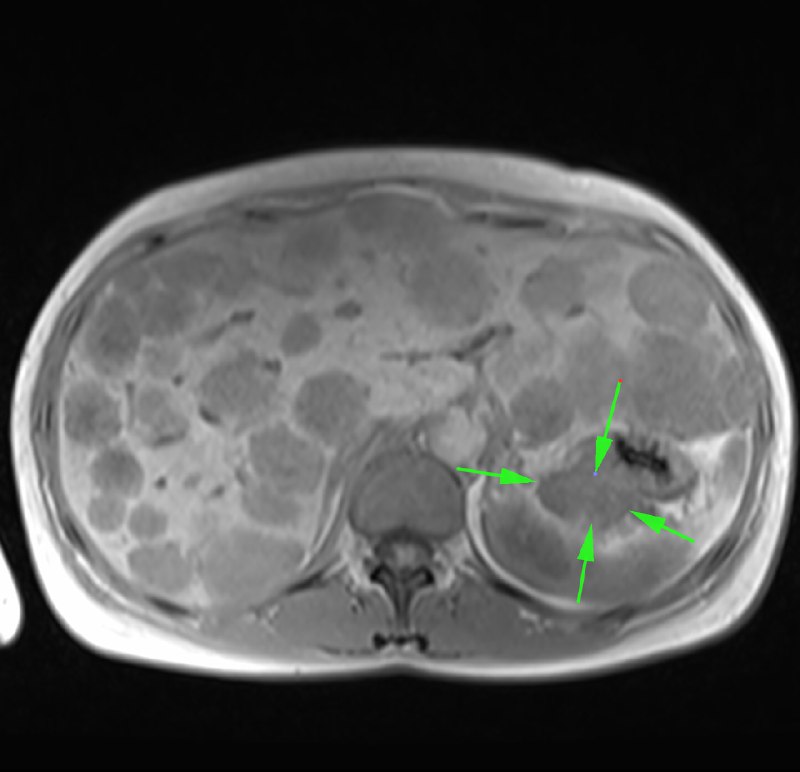

Одно из самых паскудных проявлений злокачественной опухоли - перитонеальный карциноматоз.

Средняя выживаемость при нем по одним данным составляет от 2,3 до 9 месяцев, по другим - варьирует от 11 до 17 месяцев при первичной опухоли, и зависит от стадии первичной опухоли при вторичном (стадии 0-2 - 5-10 месяцев, стадии 3-4 - 2-3,9 месяцев). Расположение первичной опухоли также может влиять на показатели выживаемости: при колоректальной карциноме средняя продолжительность жизни составляет 6,9 месяцев. Средняя продолжительность жизни при опухоли желудка составляет 6,5 месяцев.

Девушка 72 лет с карциноматозом брюшины, известно, что была гистерэктомия, а при перитонеальном карциноматозе, вызванном раком эндометрия средняя продолжительность жизни не превышает 12 месяцев, хотя при проведении циторедуктивной хирургии в сочетании с гипертермической внутрибрюшинной терапии описывают случаи продолжительности жизни и до 3 лет (интересно, что саудиты такое опубликовали, можно ли верить? Хотя, французы опубликовали, что после такого лечения аж трое пациентов прожили 7, 23 и 39 месяцев).

А у вас в местечке проводят такую терапию?